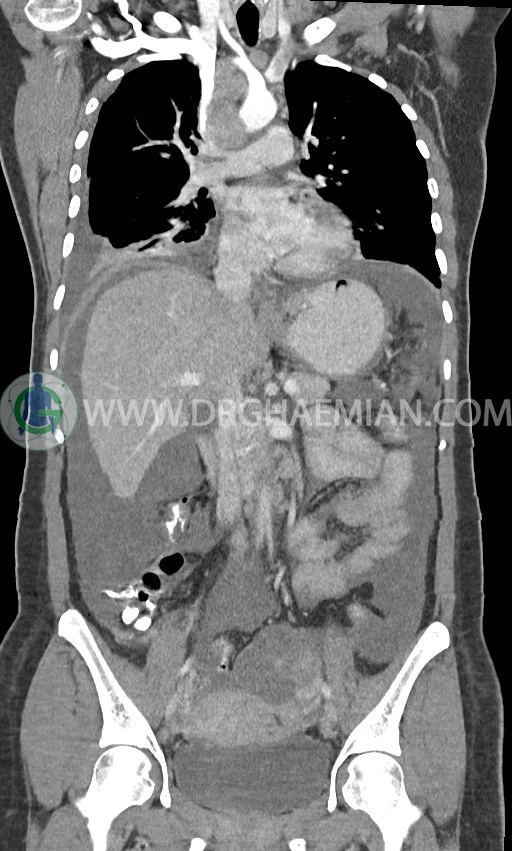

در سی تی اسکن اسپیرال ریه، مدیاستن و شکم و لگن با کنتراست خوراکی و وریدی (مولتی دیدکتور 16 با مقاطع ظریف و بازسازی های ساژیتال و کرونال) :

لنفادنوپاتی فراون با حداکثر SAD=25mm در مدیاستن

لنفادنوپاتی با حداکثر SAD = 12mm در سوپراکلاویکل چپ (level 4) و در level 6 و level 7

pleural effusion قابل توجه دوطرفه همراه با passive collapse سگمان های بازال (با شدت بیشتر در سمت راست)

توده با حدود صاف و واضح به قطر 17mm درمدیال پستان راست و با حدود لوبوله به قطر 20mm در قسمت خارجی- فوقانی پستان راست

انفیلتراسیون تومورال در قسمت های مختلف اومنتوم (omental cake)، به ویژه در قسمت تحتانی حفره شکم و لگن

توده سالید – سیستیک به ابعاد 40x60mm در تخمدان چپ و به ابعاد 20x40mm در تخمدان راست و

لنفادنوپاتی فراوان در اطراف آئورت و IVC با حداکثر SAD= 25mm در دیواره دو طرف حفره لگن با حداکثر SAD= 20mm

مشهود است.